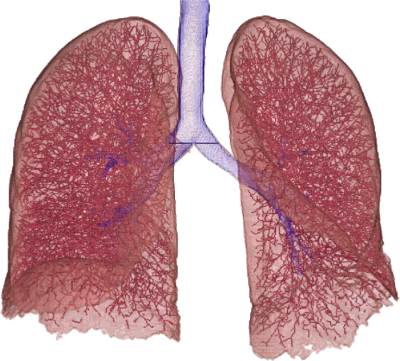

We found a correlation between DM and mPAP of (Spearman correlation coefficient, p<0.01). There was a significant difference between the DM of patients with and without PH (Table 2, p<0.05), thus enabling to discriminate the two groups on our dataset of 24 patients. Two representative vessel segmentation results of the PH study datasets are shown in Figure 7.

3.4 Contrast enhanced CT images from our clinical PH study

Our clinical application is the detection of pulmonary hypertension (PH), which is a chronic disorder of the pulmonary circulation, marked by an elevated vascular resistance and elevated mean pulmonary artery pressure (mPAP). Our hypothesis is, that the pulmonary vascular tree shows quantifiable differences between patients with and without PH. One quantifiable property of the vessels is their tortuosity, which is a readout of twistedness [3]. The most common metric of vascular tortuosity is the distance metric (DM), which provides a ratio of the actual vessel length to the Euclidean distance between its endpoints [3]. To determine the tortuosity, the lung vessel centerlines and branching points are extracted. The DM is calculated and compared with the patient’s clinical parameters.